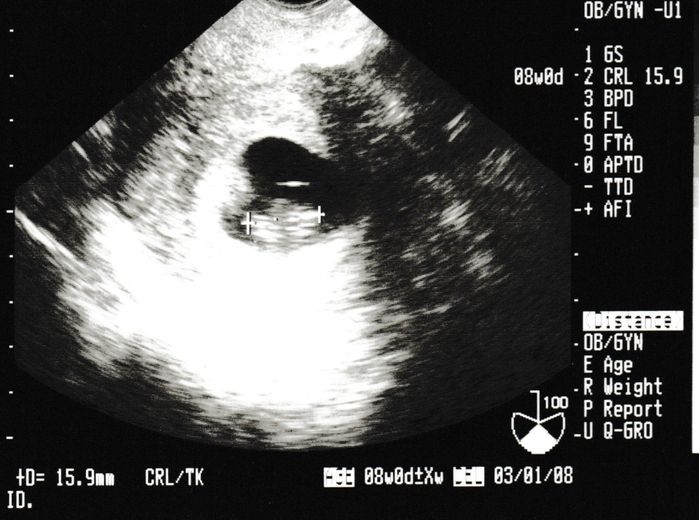

妊娠6週目のエコー写真

不安な1週間を過ごし、2回目の健診。心拍が確認できました。母子手帳取得の許可が降り、やっと妊娠したと言えるとホッとしました。安心したのもつかの間、早く分娩を申し込まないと、予約がいっぱいになるということで、里帰り出産か、今の産院かを判断しなければならず、実家近くの産院を見学したりと慌ただしい時期でした。結局、今の産院で出産してから里帰りすることにしました。